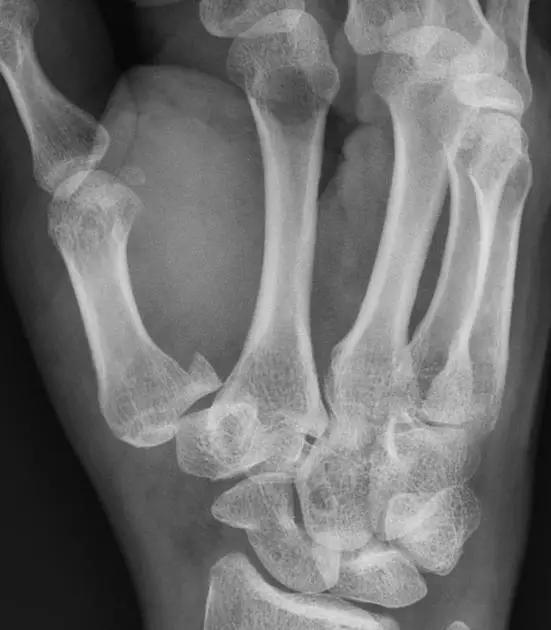

11. Buttonhole deformity/Boutonnière deformity(纽扣畸形)

伸肌腱的中央腱束断裂,使近侧指间关节突出于侧束指间,表现为近侧指间关节屈曲,远侧指间关节过伸畸形。多发生于类风湿性关节炎后畸形。

(来源:OrthoInfo- AAOS)

(来源:Medscape)